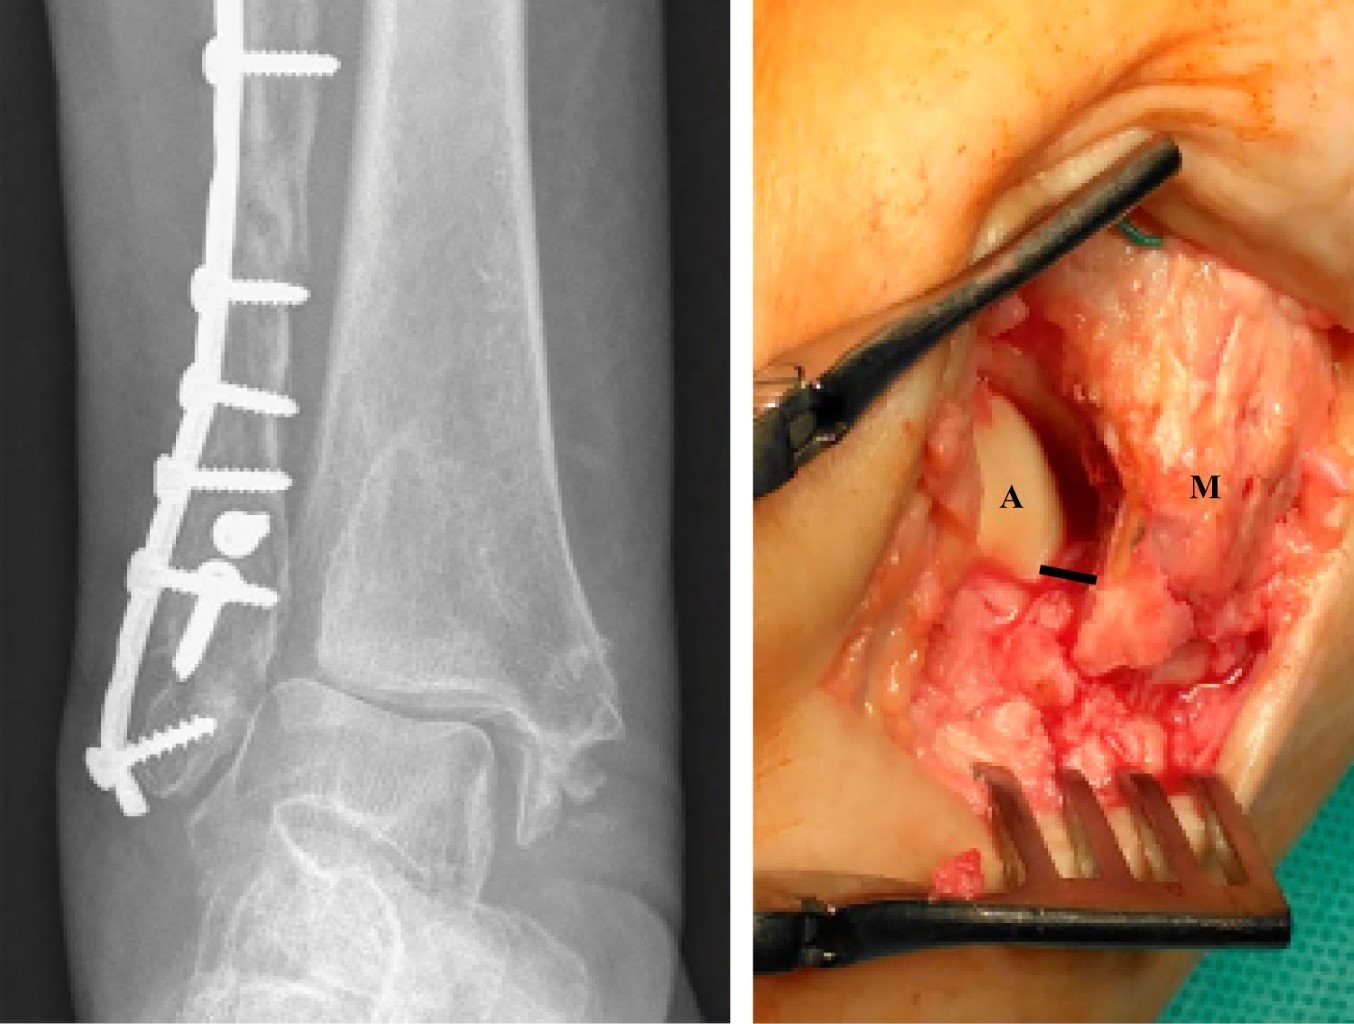

Surgical tecnhique: An antero-medial approach to the ankle joint is made. The deltoid ligament is first detached at its anterior medial malleolus insertion, and the "box resection" is then applied: the articular (lateral) facet of the medial malleolus is removed with an osteotome in vertical alignment. The amount of bone resection should be the necessary for the talus to correctly realign with the tibial plafond. To complete the "box resection", the most lateral 1 or 2 mm of the distal tibial plafond are removed with a small osteotome introduced in a horizontal orientation. A new "shoulder" is created for the talus to get back to its original position. With the talus repositioned, we proceed with correcting the previous malunited syndesmosis. The syndesmosis is reduced with a clamp and fixed with a flexible system, with the ankle in neutral position. An open syndesmosis debridement is required if the fibrous tissue is compromising anatomical reduction.

The patient was submitted to hardware removal but the dorsiflexion block persisted. As our goal was to remove the dorsiflexion mechanic block and to restore tibiotalar congruency, we decided to perform the "box resection" (Figure 4 and 5). This allowed an immediate medial talus translation. A syndesmosis debridement and open reduction with a clamp was performed and stabilized with a flexible system (TightRope® Arthrex). We conducted a deltoid ligament re-insertion with anchors (Figure 6). At the end of the procedure, complete dorsiflexion was accomplished with a stable range of motion. Tibiotalar congruency was confirmed in the AP radiograph (Figure 7).

After hardware removal, the medial translation of the talus was again impossible due to a mechanical block by the malunited medial malleolus. We performed the "box resection" following the same steps used for syndesmosis reduction and fixation and deltoid repair. An oblique osteotomy of the fibula was performed to regain correct length and alignment. Articular congruency was obtained with a stable full range of motion. The final result shows a congruent joint (Figure 10).